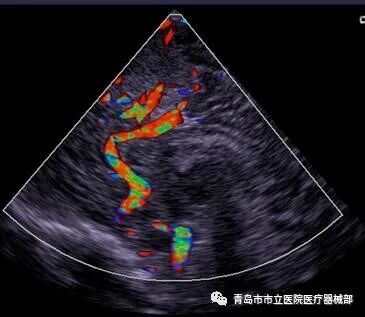

3.4.4彩色血流成像(CFM

彩色多普勒血流显像(CDFI)或彩色多普勒显像(CDI)主要是利用血液中运动的红细胞对声波的散射,产生多普勒效应,经伪彩色编码技术,在二维图像上显示彩色血流影像。其与脉冲多普勒一样的原理,不同的是脉冲多普勒表示一小段深度的血流速度随时间的变化;而CFM法是用色彩来表示沿接收信号声束多个部位(深度)的血流速度,并叠加在B超图像上,其特征是可以发现异常血流(反流、动静脉短路等)。CFM法显示主要分为速度显示法、速度-离散显示法。

速度显示法:血流方向由红色(朝向探头的血流)、蓝色(远离探头的血流)来表示。速度快慢由红色变为黄色、蓝色变为蓝绿色的色彩变化来表示。

速度-离散显示法:血流方向由红色、蓝色来表示,速度快慢由不同颜色的亮度来表示,速度紊乱(分散)以绿色来表示,能清楚显示瓣膜反流等快速血流,主要应用于循环系统检查。